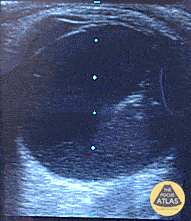

Orbital - Posterior Vitreous Hemorrhage

Posterior Vitreous Hemorrhage Painless visual field cut with position change. Posterior vitreous hemorrhage with organization and dynamic movement gong over the top of the optic nerve, but not involving it to suggest retinal detachment. Dr. Dustin Morrow